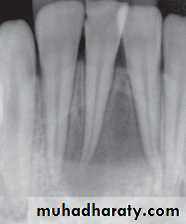

Tracing the sinus tract will provide objectivity in diagnosing the location of the problematic tooth. To trace the sinus tract, a size #25 or #30 gutta-percha cone is threaded into the opening of the sinus tract

UNIVERSITY OF MOSUL